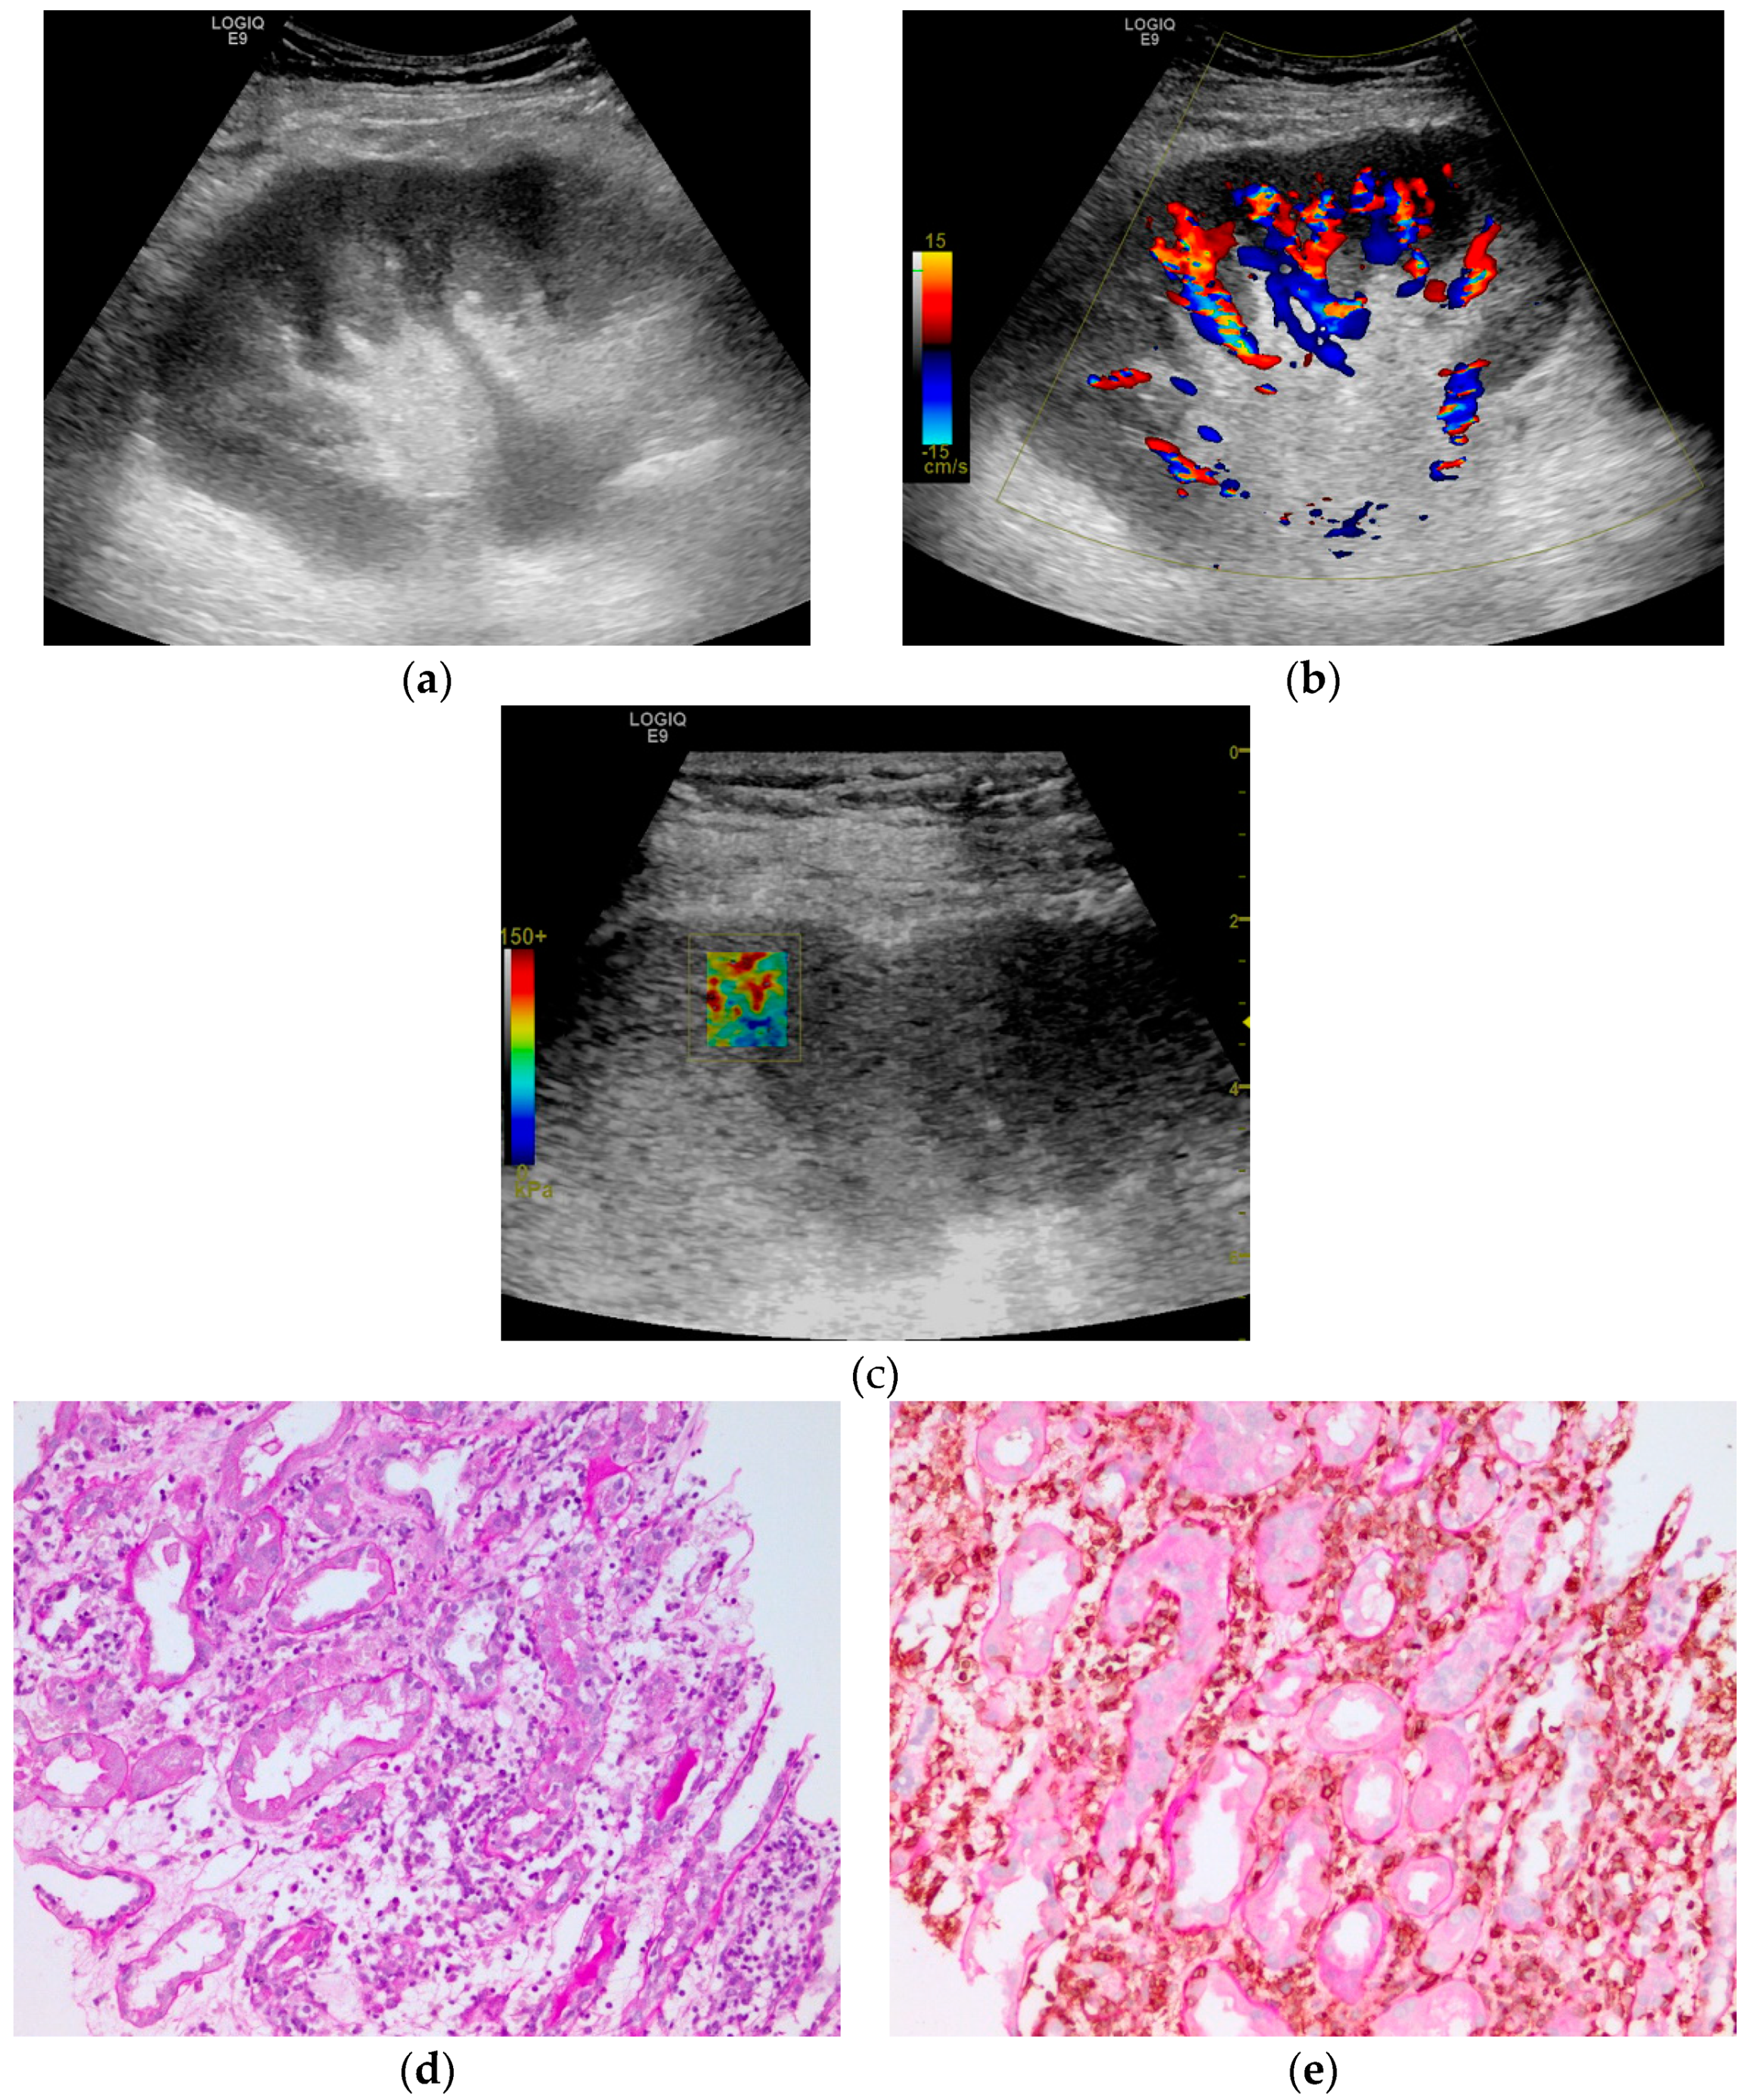

2.4. Shear Wave Elastography Examination